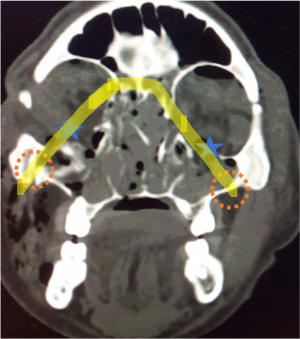

| Invasive Sino-orbital fungal disease[15] | Immunocompromised (mucormycosis)

Imuunocompetent (aspergillosis) |

Severe limitation of EOM with associated chemosis and blepharoptosis.

In mucormysosis, very acute progression of disease with presence of black nasal fliuid, eschar or skin discoloration (characteristic). On fundus examination, CRAO present. In aspergillosis, sub acute progression. |

CT- lobulated soft tissue msses, opacification of paranasal sinuses with high attenuation content with enhancing adjacent orbital soft tissue

T1- low to high intensity T2- marked hypointensity |